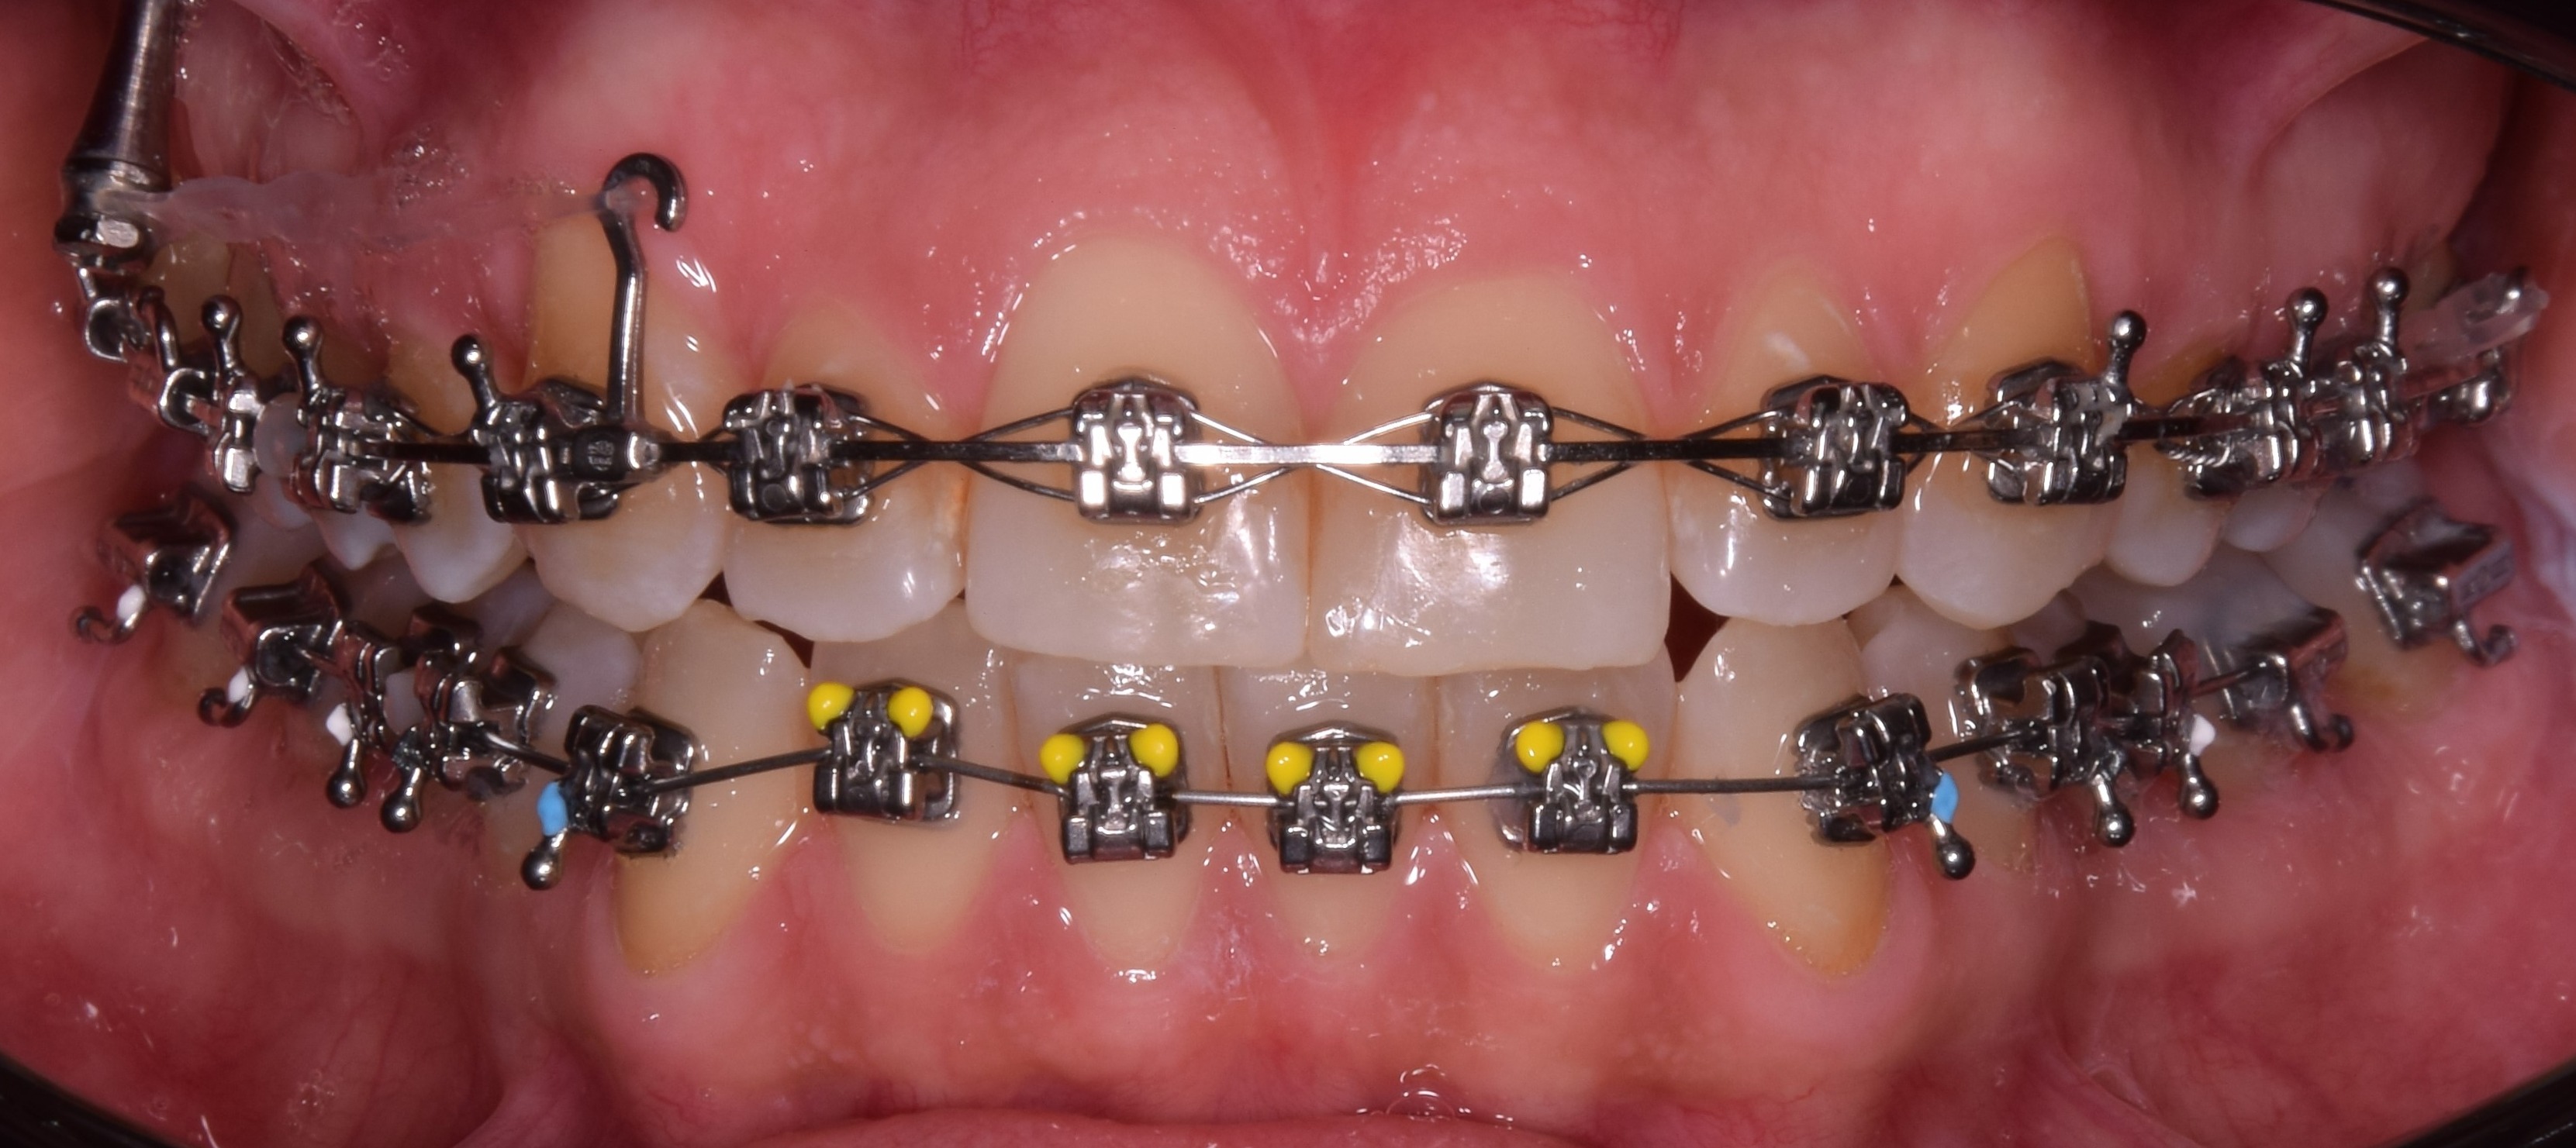

Rögzített fogszabályozó és MRI – lehetséges interferencia

A legfrissebb kutatások – például a BMC Oral Health-ben megjelent tanulmány – szerint a rögzített fogszabályozó készülékek befolyásolhatják az MRI vizsgálat minőségét, különösen akkor, ha a vizsgálat a fej vagy a nyak területére irányul. A fém alkatrészek torzításokat (ún. artefaktokat) okozhatnak a képeken, ami nehezítheti vagy ellehetetlenítheti a pontos diagnózist.

A tanulmány alapján:

• Az MRI képeken jelentkező torzulás mértéke attól függ, milyen anyagból készült a fogszabályozó.

• A rozsdamentes acélból készült elemek nagyobb mértékben torzítják a képet, mint például a titánból vagy kerámiából készült változatok.

• A mágneses tér erőssége (pl. 1,5T vagy 3T MRI) szintén befolyásolja a torzítás mértékét.